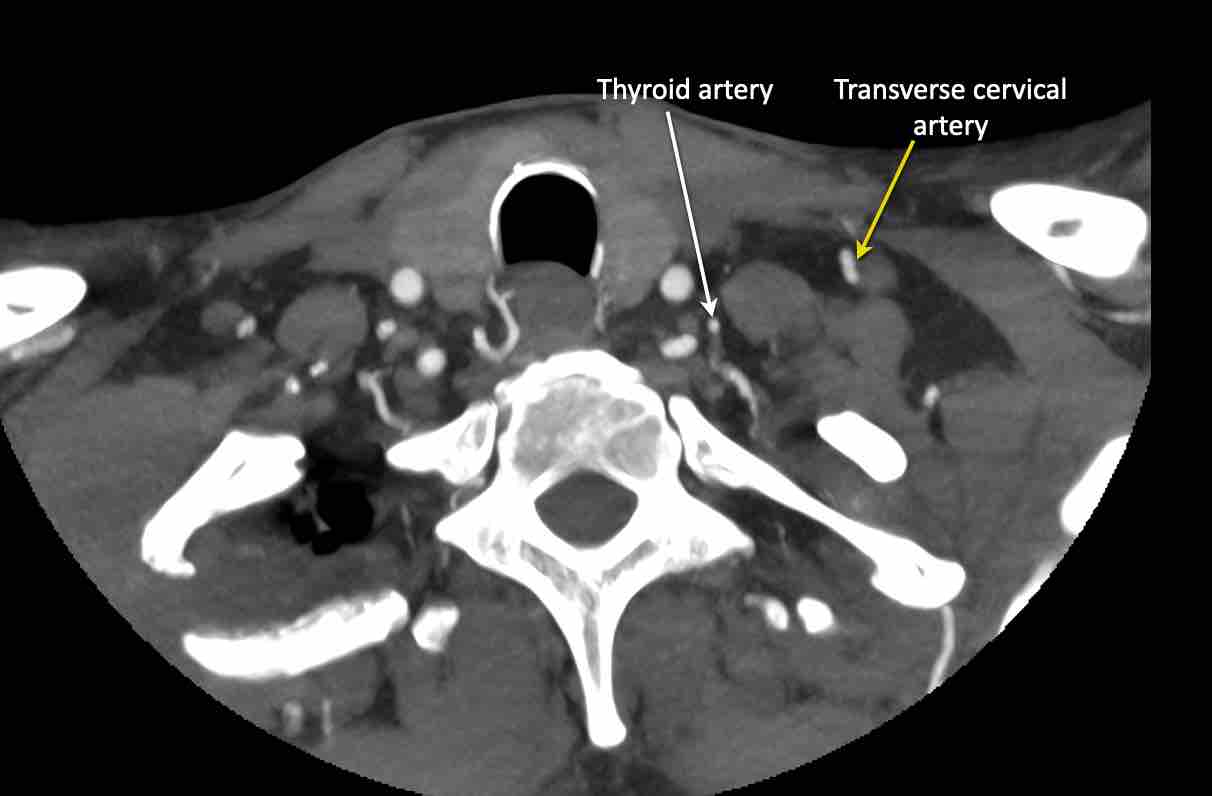

Động mạch cổ ngang

Cuộn qua các hình ảnh để xem giải phẫu của động mạch cổ ngang.